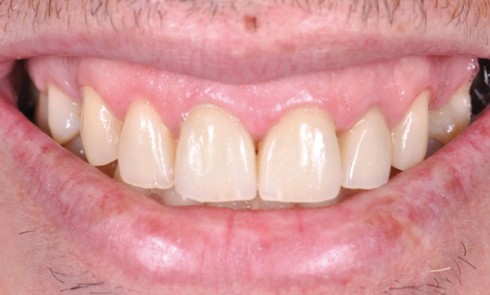

Cet article présente le concept de Régénération Prothétique Guidée (RPG) sur piliers dentaires (fig. 1). Le diagnosticDans la zone antérieure maxillaire,...